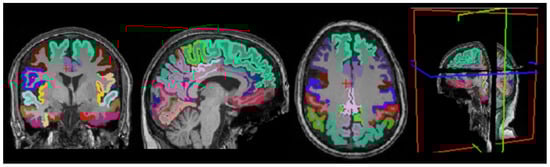

3.4. Cortical Structure Segmentation Results